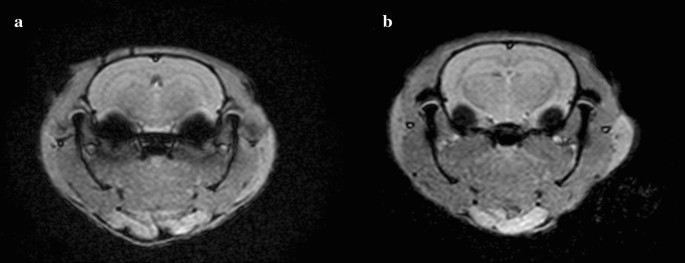

The induction of repetitive mTBI was conducted for 3 consecutive days (days 1–3) in all rats (Fig. 1). mTBI was induced in rats using a modified weight-drop device and a protocol previously described by Tang et al. [19]. A 175 g steel weight was briefly dropped from a height of 30 cm through a polyvinyl chloride tube with an inner diameter of 11 mm terminating on the bregma of the rat. The rat was placed on a wooden plate and fixed with Velcro in the prone position. To evaluate the possibility of a skull fracture or brain hemorrhage, we conducted brain MRI study on all rats after completing the study on day 5. The rats were anesthetized with Zoletil® and placed in a 5 cm inner diameter, 4-element phased-array, animal-dedicated surface coil (Chenguang Medical Technology, Co., Ltd, Shanghai, China). The strength of the MRI magnet was 3 T. The MRI protocol used was a T2-weighted image sequence (repetition time/echo time = 650/22). The slice thickness was 3.0 mm and the matrix scan size was 512 × 512 pixels. Brain MRI showed no significant pathological features, such as skull fracture, brain hemorrhage, or diffuse axonal injury after repetitive mTBI (Fig. 2a, b). The histological examination was performed to rule out the presence of brain damage resulting from repetitive mTBI at day 5. Brains of rats were removed and fixed in 10% neutral buffered formalin after being euthanized in a closed chamber with 10% carbon dioxide. Coronal brain Sects. 15 µm thick were cut using a microtome, mounted on glass slides, and stained with hematoxylin and eosin. Light microscopy was used for evaluating morphological changes in brain tissue at 100 × magnification. Histochemical analysis showed no visible morphological changes in either the control or tDCS groups (Fig. 3a, b).

Experimental arrangement and the position of electrodes during tDCS. a Experimental arrangement. Before induction of repetitive mTBI (day 1), MEP and behavioral tests are performed on the rat model. After pre-mTBI tests, the first mTBI is induced in the rat models. On days 2 and 3, second and third mTBI is induced in the rats to establish the repetitive mTBI rat models. After the third mTBI, MEP, and motor coordination studies are done (day 3). On day 4, anodal tDCS at M1 area is applied to the tDCS group. On day 4, 1 h after tDCS, MEP is done. On day 5, behavioral tests and brain MRI are done. b The position of anodal and cathodal electrodes during anodal tDCS. Circle means anodal electrode and square means cathodal electrode. Cup-shaped anodal electrode was attached to the skin over the left M1 area, and rectangular rubber cathodal electrode was positioned on the trunk